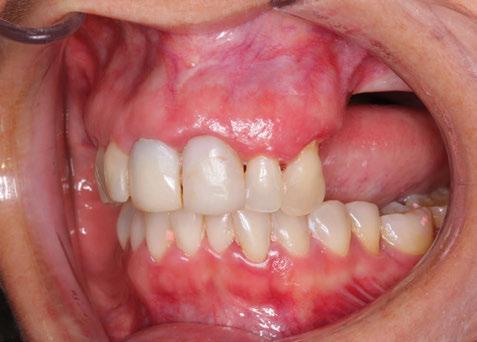

directamente a cabeza de implante para realizar una prótesis dentoalveolar de cerámica de 3 piezas, que equilibraran la oclusión y dieran soporte al labio y la mejilla (Figuras 14-17)

Durante el primer mes tras la intervención la paciente presentó epífora del ojo izquierdo que se resolvió de forma espontánea. Al año acude a consulta refiriendo dolor localizado y celulitis subcutánea originada por tejido de granulación en el brazo de la conexión más anterior.

Tras realizar curetaje quirúrgico periimplantario y tras una semana

de tratamiento antibiótico con amoxicilina y ácido clavulánico, cede la infección. Al segundo año de seguimiento, el tratamiento permanece estable y no ha presentado más complicaciones biológicas, estructurales o protésicas.

Figura 14. Imagen intraoral frontal postoperatoria al año de la reconstrucción.

Figura 15. Detalle de prótesis dentoalveolar cerámica en visión lateral.